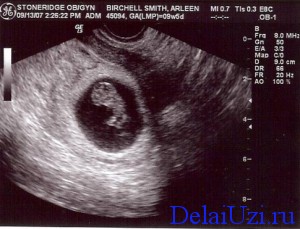

Коли в родині очікується поповнення, звичайно ж, всі сподіваються тільки на хороше і найголовніше - це здоров'я малюка і мами. Для того щоб знати точно, що з маленькою людиною все гаразд, необхідно пройти планове УЗД на терміні 9 тижнів.

До пологів потрібно проходити ультразвукове дослідження, яке покаже, як розвивається дитина. На 9 тижні вагітності,у плода продовжує формуватися головний мозок, з'являється чітка форма особи, можна розрізнити вушні раковини і розріз очей. У цей період починають розвиватися статеві органи, але фахівець УЗД ще не може точно визначити стать.

Крім того, на 9 тижні харчування дитини починає здійснюватися через пуповину. Завдяки ультразвукового дослідження, можна визначити загальний стан дитини, почути його серцебиття і побачити, як рухаються руки. На цьому етапі, у малюка починають формуватися пальчики на руках і ногах, але нижні кінцівки поки ще слабо рухаються, за рахунок того, що верхні кінцівки розвиваються швидше. Проходити таке обстеження слід для того, щоб виявити будь-які порушення в розвитку дитини.